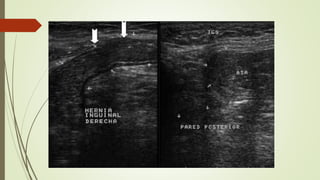

ECOGRAFÍA

 Transductor lineal 7 – 10 MHz

 Escala de grises:

 Asas intestinales con peristaltismo dentro de la hernia inguinal.

 Supino / bipedestación / Valsalva

Valsalva:

 Hernia inguinal directa: plexo pampiniforme distendido se

ve desplazado por el saco herniario.

 Hernia inguinal indirecta: ingurgitación alterada del plexo

pampiniforme.

 Doppler color:

 Demuestra la arteria epigástrica inferior y la relación con el saco

herniario.

 Hernia estrangulada.

HERNIA DIRECTA

 Pasa anteromedial a vasos epigástricos inferiores

 Masa lateral a músculo recto

 «Signo lateral cresciente»

 CI desplazado y comprimido lateralmente, incluyendo grasa y demás

contenidos

HERNIA INDIRECTA

 Pasa superolateral a vaso epigástrico inferior  lateral y medial

siguiendo el CI

 Se muestra con el contenido habitual del CI, no se comprime ni

distorsiona